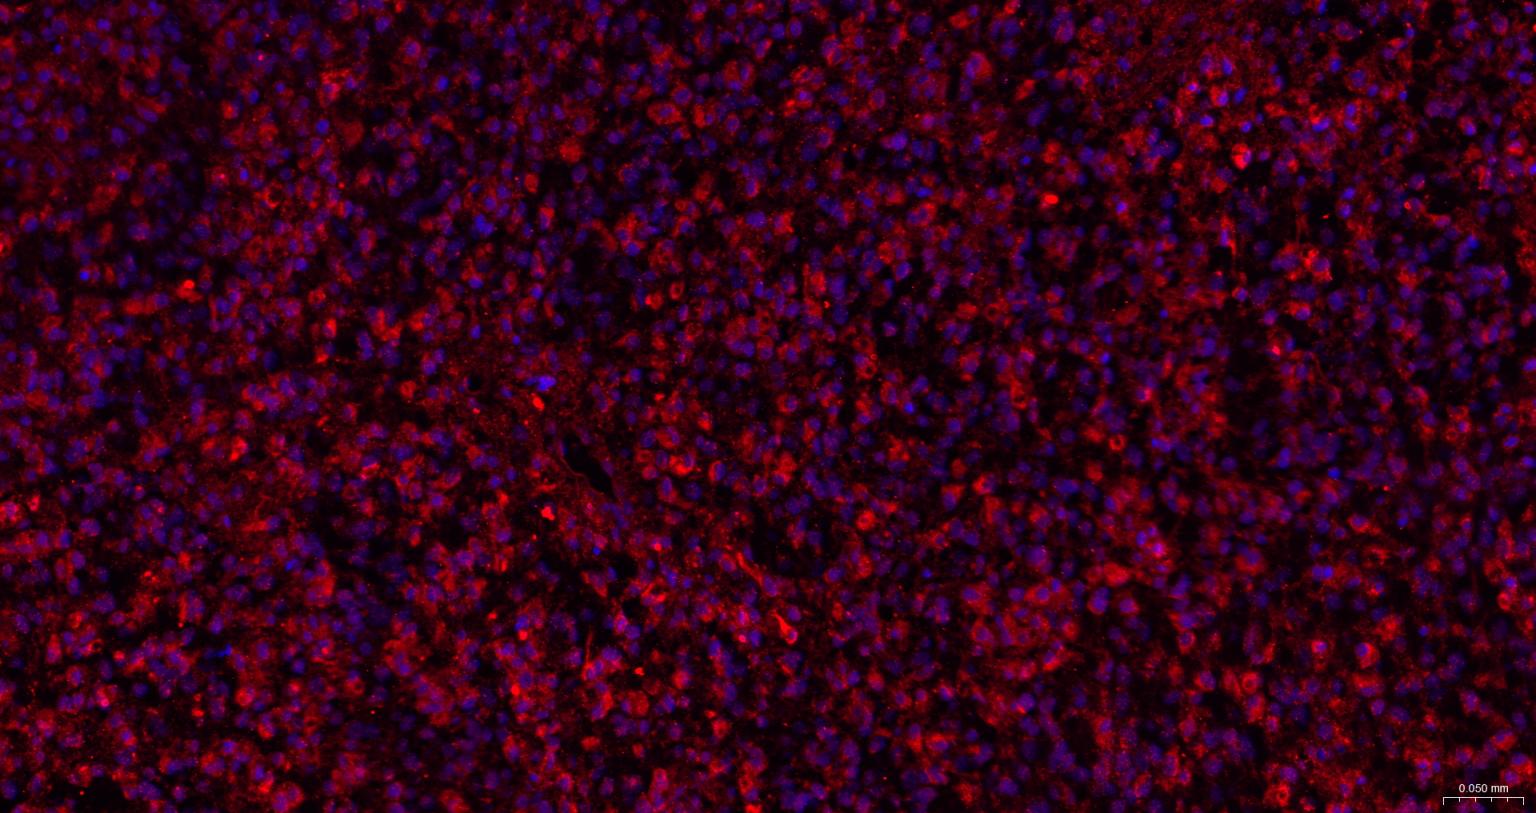

| IHC-P | Human, Mouse, Rat, Rabbit, Pig, Cow, Dog, Horse | 1:100-500 | |

| IHC-F | Human, Mouse, Rat, Rabbit, Pig, Cow, Dog, Horse | 1:100-500 | |

| IF | Human, Mouse, Rat | Rabbit, Pig, Cow, Dog, Horse | 1:100-500 |

交叉反应: Human, Mouse, Rat (predicted: Rabbit, Pig, Cow, Dog, Horse)